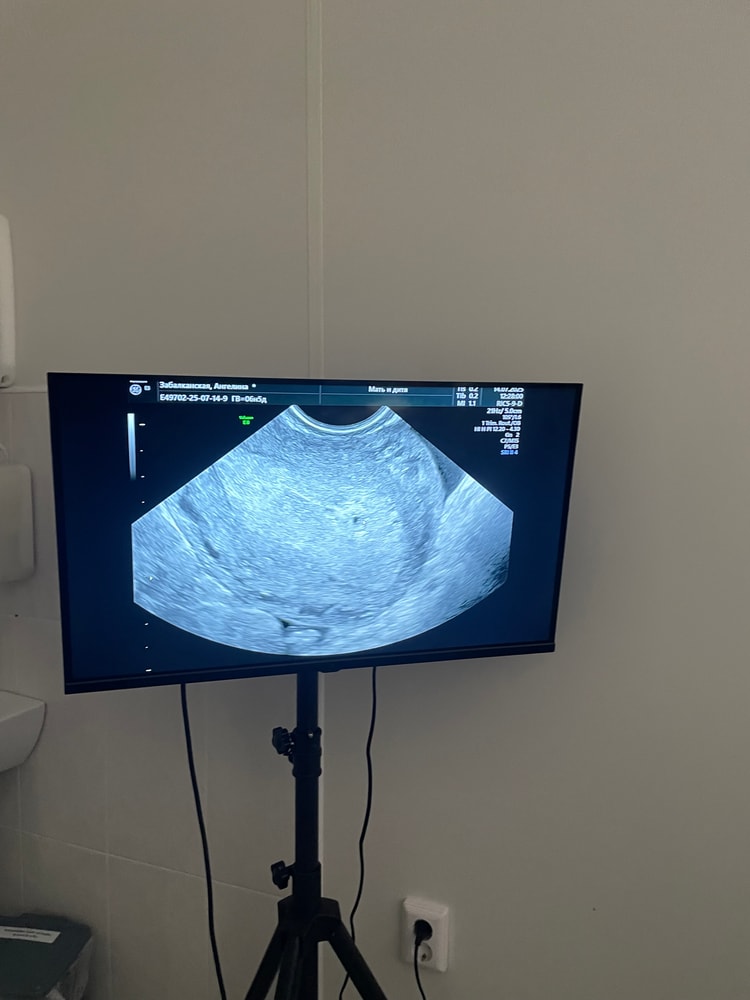

Цикл не восстановился, после родов, дату зачатия не знаю, но врач предположил что сейчас 4-5 неделя акушерская, возможно внематочная в левой трубе, она расширена, может у кого была похожая ситуация как все вышло, в матке есть маленькая точка 2 мм, возможно пя

Ника, там где была овуляция, трубы нет, была удалена, уже была внематочная, сказали что яйцеклетка, переплыла в левую трубу